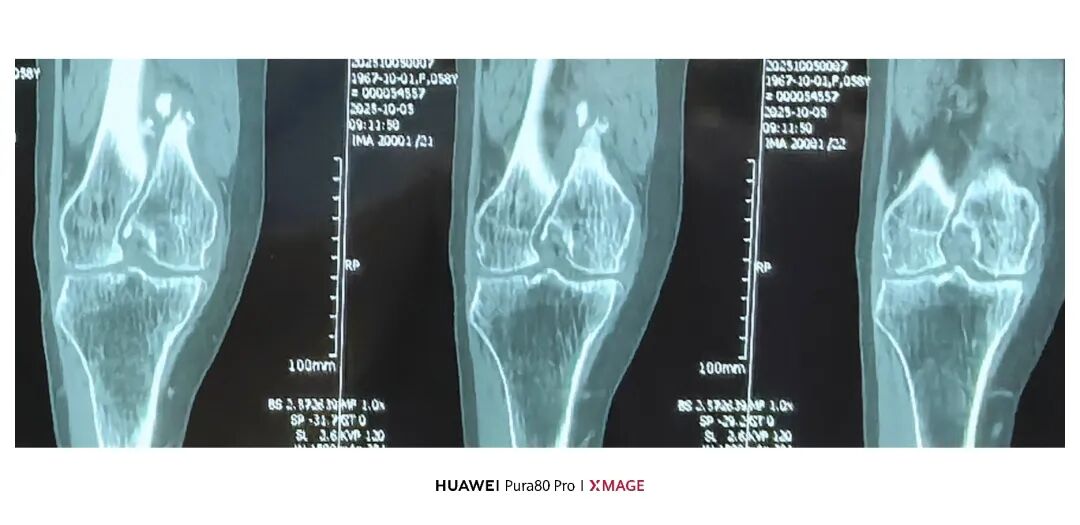

5个月前在魔都骨折,当时建议手术

患者拒绝并签字

给予支具固定

现畸形、疼痛伴活动受限来院

复位满意,力线纠正